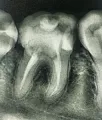

Подскажите, пожалуйста, нормально ли, что после лечения зуб продолжает болеть? Вот уже третий день после того, как поставили пломбу, а зуб ноет, особенно по ночам и при накусывании/нажатии (боль несильная, но неприятно). Из зуба доставали нерв и запломбировали канал.

Судя по Вашим симптомам, у Вас прогрессирует обострение периодонтита. То есть у Вас неправильно поставлен диагноз, и соответственно, некорректное лечение.